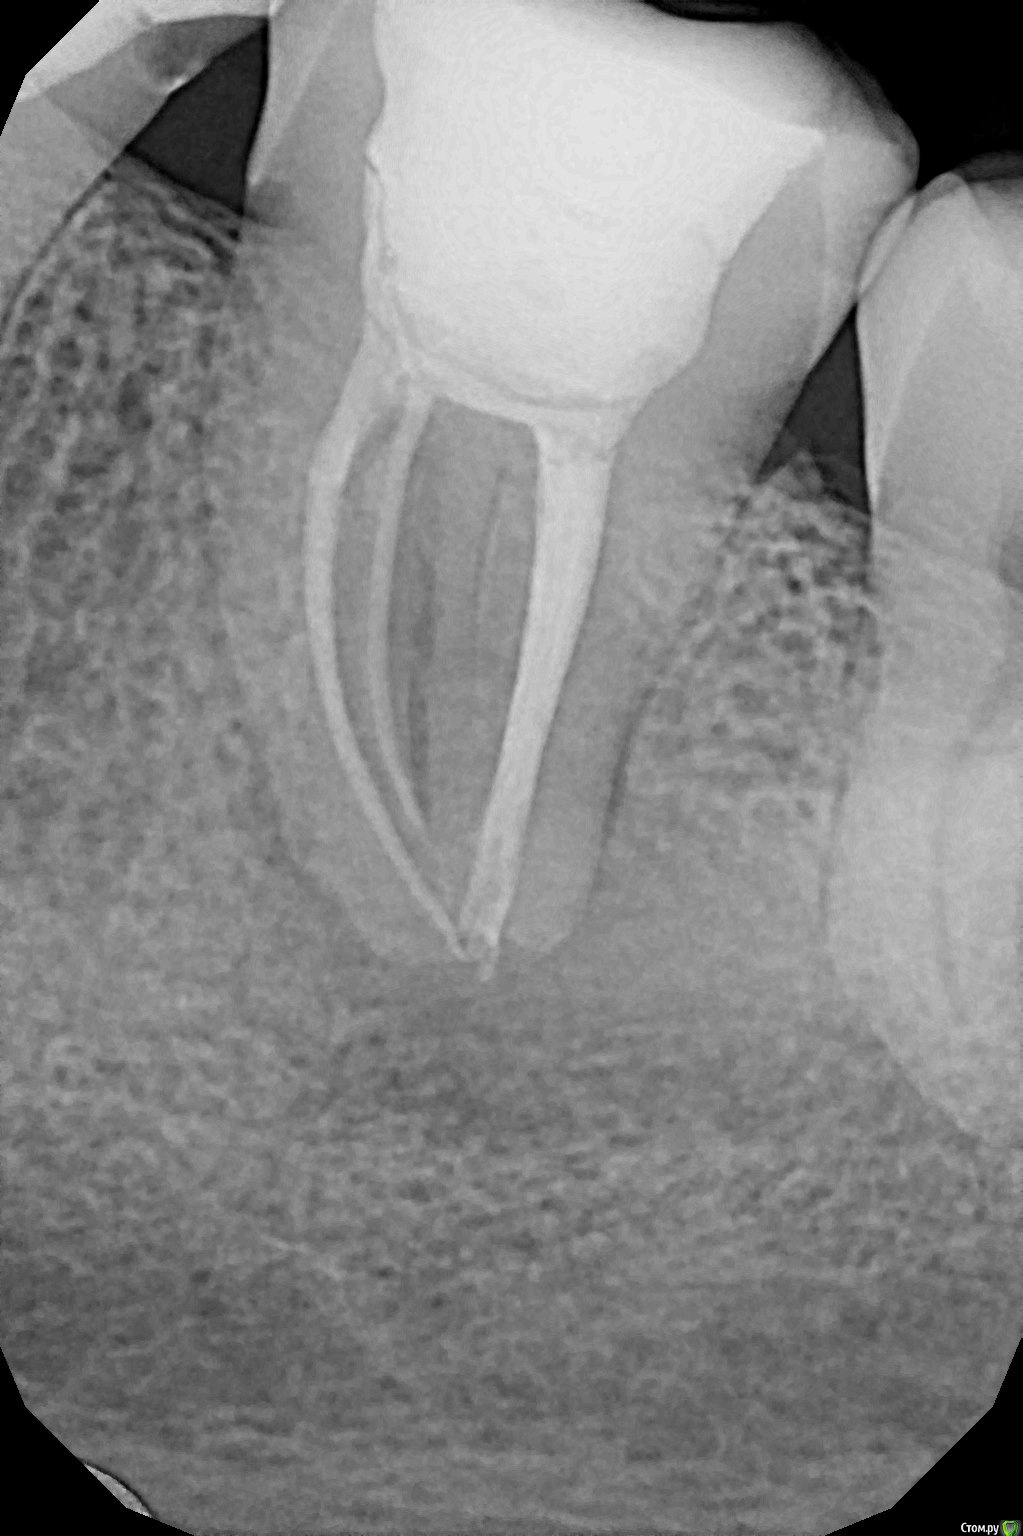

Chef Опубликовано 11 сентября, 2015 Поделиться Опубликовано 11 сентября, 2015 При осмотре у стоматолога (частный кабинет у дома) обнаружился свищ с внешней стороны десны у нижней семерки слева (37 ?), сделали снимки, на нём гранулема или киста у леченого ранее зуба.Из свищевого хода при надавливании выходит гной, а так зуб не как не беспокоит.Она предложила удалить зуб.Да еще и напугала, что при есть вероятность задеть общий нерв и в результате получить онемение части лица (?). Меня как-то всё это смутило... Я пошел в другую клинику проконсультироваться, там сказали, что можно попробовать перелечить проблемный зуб, но гарантии 50/50, что смущает, хотелось бы более уверенный прогноз результата.Там у них нет микроскопа и врача работающего с ним, эдодонтиста, просто терапевт общей практики.Я не решился на лечение у них. Подскажите, можно этот зуб вылечить? Снимки выкладываю. Ссылка на комментарий

St. Опубликовано 11 сентября, 2015 Поделиться Опубликовано 11 сентября, 2015 3.6 и 3.7(второй и третий с конца) перелечить и коронки. 100% гарантии на повторное лечение каналов не бывает в принципе, и вобщем-то микроскоп - штука нужная и полезная, но далеко не панацея. 3 Ссылка на комментарий